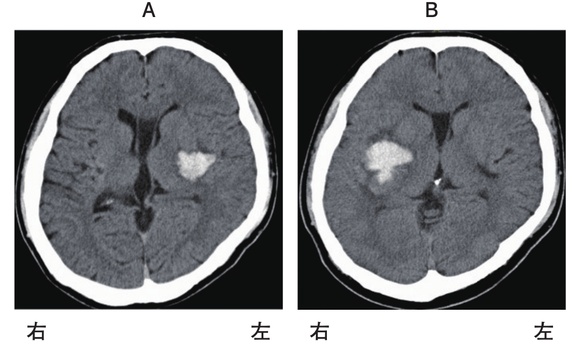

42 歳の男性。右利き。自営業。 3 年前に脳出血発症後、回復期リハビリテーション病院を経て自宅退院し復職したが、仕事中に再発した。初発時の頭部 CT と再発時の頭部 CT を別に示す。再発時の新たな症状として最も考えられるのはどれか。

1

昏睡

2

構音障害

3

右同名半盲

4

回転性めまい

5

Gerstmann 症候群